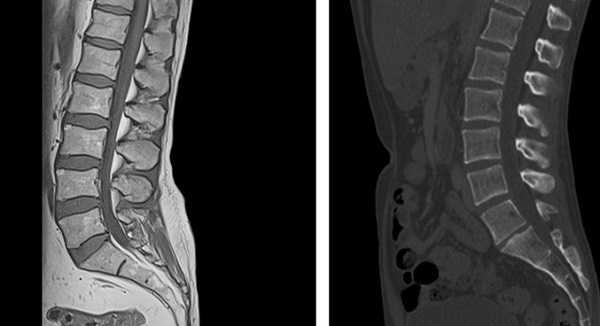

МР- и КТ- снимки поясничного отдела позвоночника

Выбирая МРТ или МСКТ, врач учитывает цели исследования. Если нужно изучить строение мягких тканей, внутренних органов, сосудов, предпочтение отдают магнитно-резонансной томографии. Рыхлые, богатые водой анатомические структуры, лучше просматриваются на МР-снимках.

Рентгеновские методы наиболее информативны относительно костной ткани и органов с неоднородной структурой (легкие и т.п.). При необходимости применяют контрастное усиление препаратами йода. Если предстоит выбрать МРТ или МСКТ, врач учитывает цели диагностики и потенциальные риски.